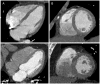

Methods: In 348 patients from the Rule Out Myocardial Infarction Using Computer Assisted Tomography trial, 64-slice computed tomography was performed and LVM measured at end-diastole. We used three LVM indexation criteria to obtain three cohorts: LVM indexed to body surface area by echocardiography (n = 337) and computed tomography criteria (n = 325), and by height (n = 326). The cohorts were subdivided into concentric remodeling and normal geometry. Extent of coronary plaque was classified based on a 17-segment model, treated as a continuous variable, and stratified into three groups: zero segment, one to four segments, and more than four segments.

Results: Patients with more than four segments of coronary plaque had higher LVM (Delta12.8-15.1 g) and LVMi (Delta4.0-5.5 g/m and Delta2.2 g/m) than those without CAD (all P < or = 0.03). After multivariable adjustment, LVM and LVMi remained independent predictors of extent of coronary plaque, with 0.27-0.29 segments more plaque per 20 g increase of LVM (all P = 0.02), 0.32-0.34 segments more plaque per 10 g/m increase of LVMi (both P = 0.02), and 0.80 segments more plaque per 10 g/m increase of LVMi (P = 0.008). Concentric remodeling patients had 1.1-1.3 segments more plaque than those with normal geometry (all P < or = 0.05). Patients with more than four segments of plaque had two-fold increase in odds (all P < or = 0.05) of having concentric remodeling as compared with those without CAD.